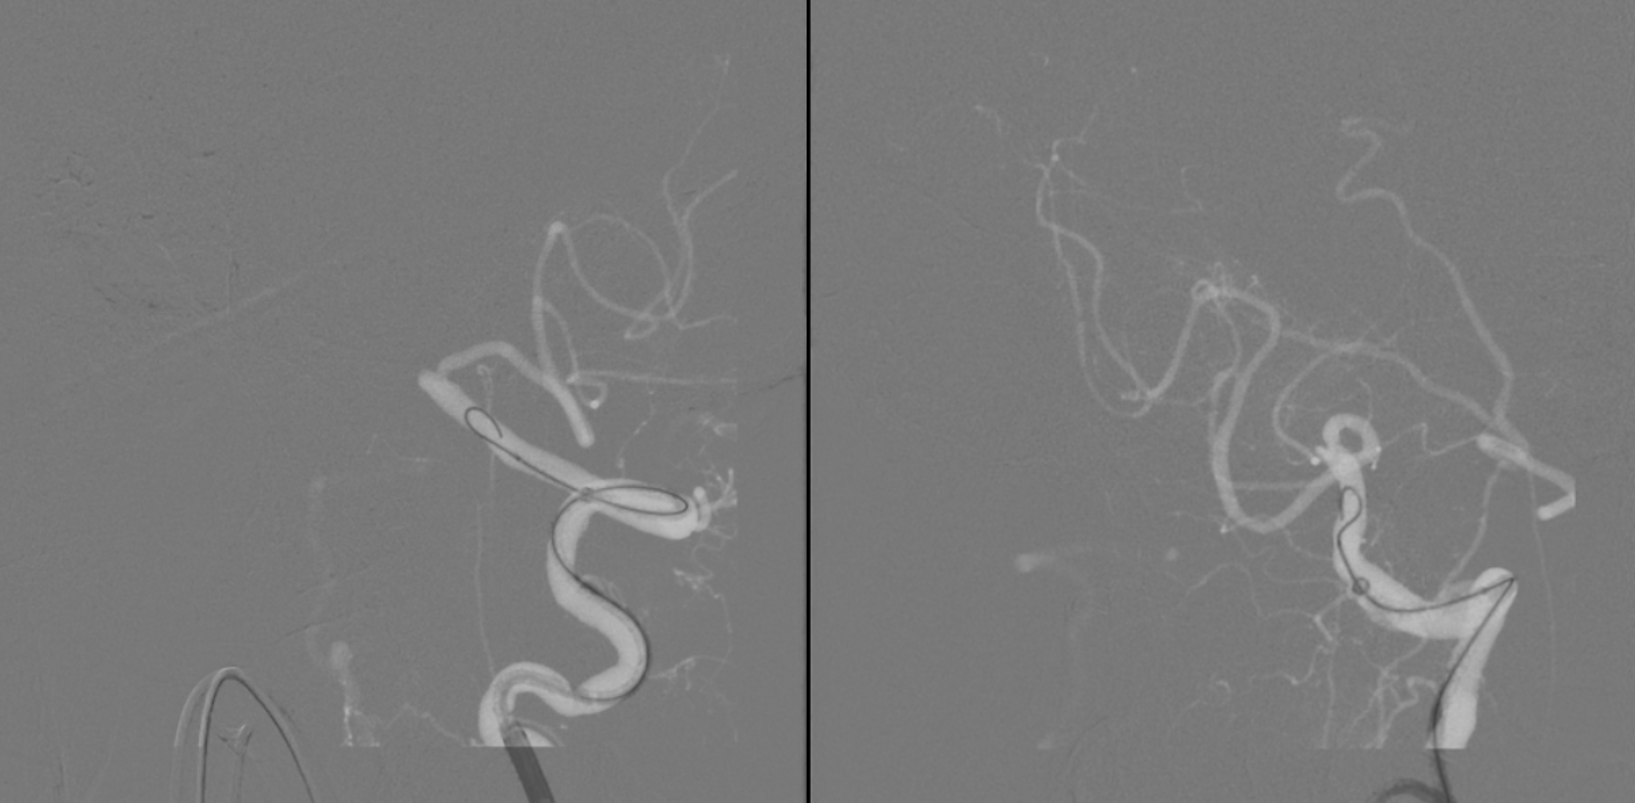

Back with a vengeance

At first wire goes into subintimal channel — see how it stays on the side and does not advance in the movie below?

Now the good way